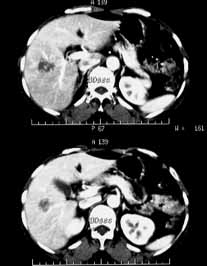

肝血管瘤06

女性,55岁,右上腹间有隐痛不适半年余。

ct诊断:肝右前叶下段血管瘤。